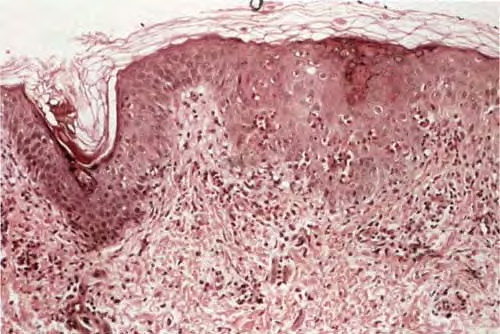

The alterations in the second stage consist of acanthosis, irregular papillomatosis, and hyperkeratosis. Intraepidermal keratinization, consisting of whorls of keratinocytes and of scattered dyskeratotic cells, is often more pronounced than in the first stage. The basal cells show vacuolization and a decrease in their melanin content. The dermis shows a mild, chronic inflammatory infiltrate intermingled with melano-phages. This infiltrate extends into the epidermis in many places.

The disorder has four stages. The first stage, consisting of erythema and bullae arranged in lines, either is present at birth or starts shortly thereafter. The extremities are predominantly affected. There is also marked blood eosinophilia. In the second stage, which occurs after about 2 months, the vesicular lesions gradually are superseded by linear, verrucous lesions that persist for several months. As the verrucous lesions subside, widely disseminated areas of irregular, spattered, or whorled pigmentation develop. This pigmentation, representing the third stage, is most pronounced on the trunk (Fig. 6-42A). It diminishes gradually after several years and may even clear completely. The fourth stage is seen in adult females. Subtle, faint, hypochromic or atrophic lesions in a linear pattern are most apparent on the lower extremities.